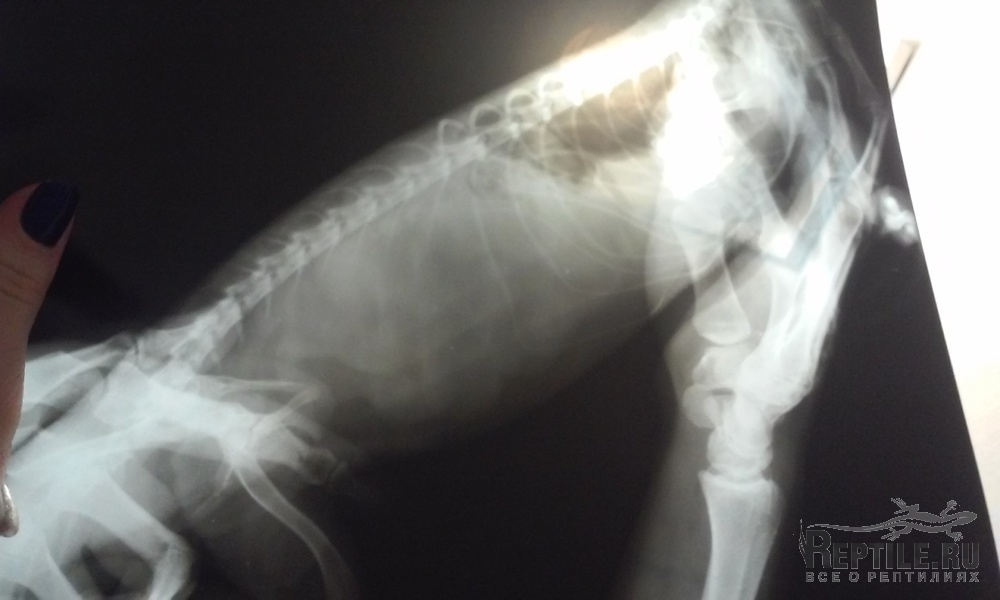

сегодня сделали рентген

что скажете??похоже на яйца?

?похоже на яйца?

Оно и есть. Скорее фолликулы, чем яйца